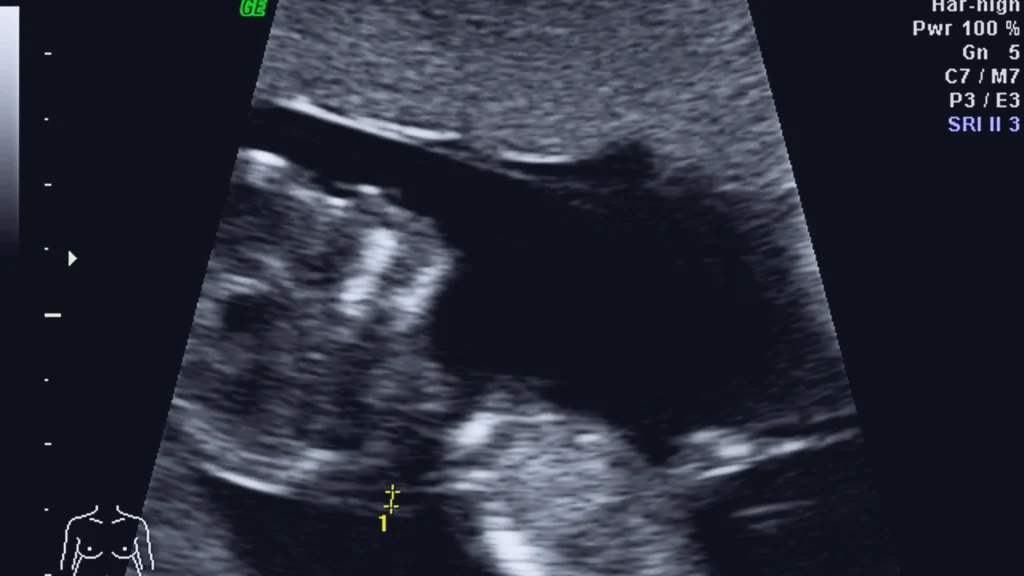

Pregnancy ultrasounds are one of the most recognised uses of this technology.

They help identify:

● Fetal heartbeat

● Expected due date

● Growth and positioning

● Placental health

● Developmental concerns

Due to the non-radiation and sound waves used in ultrasound, the test is the gold-standard imaging in pregnancy.